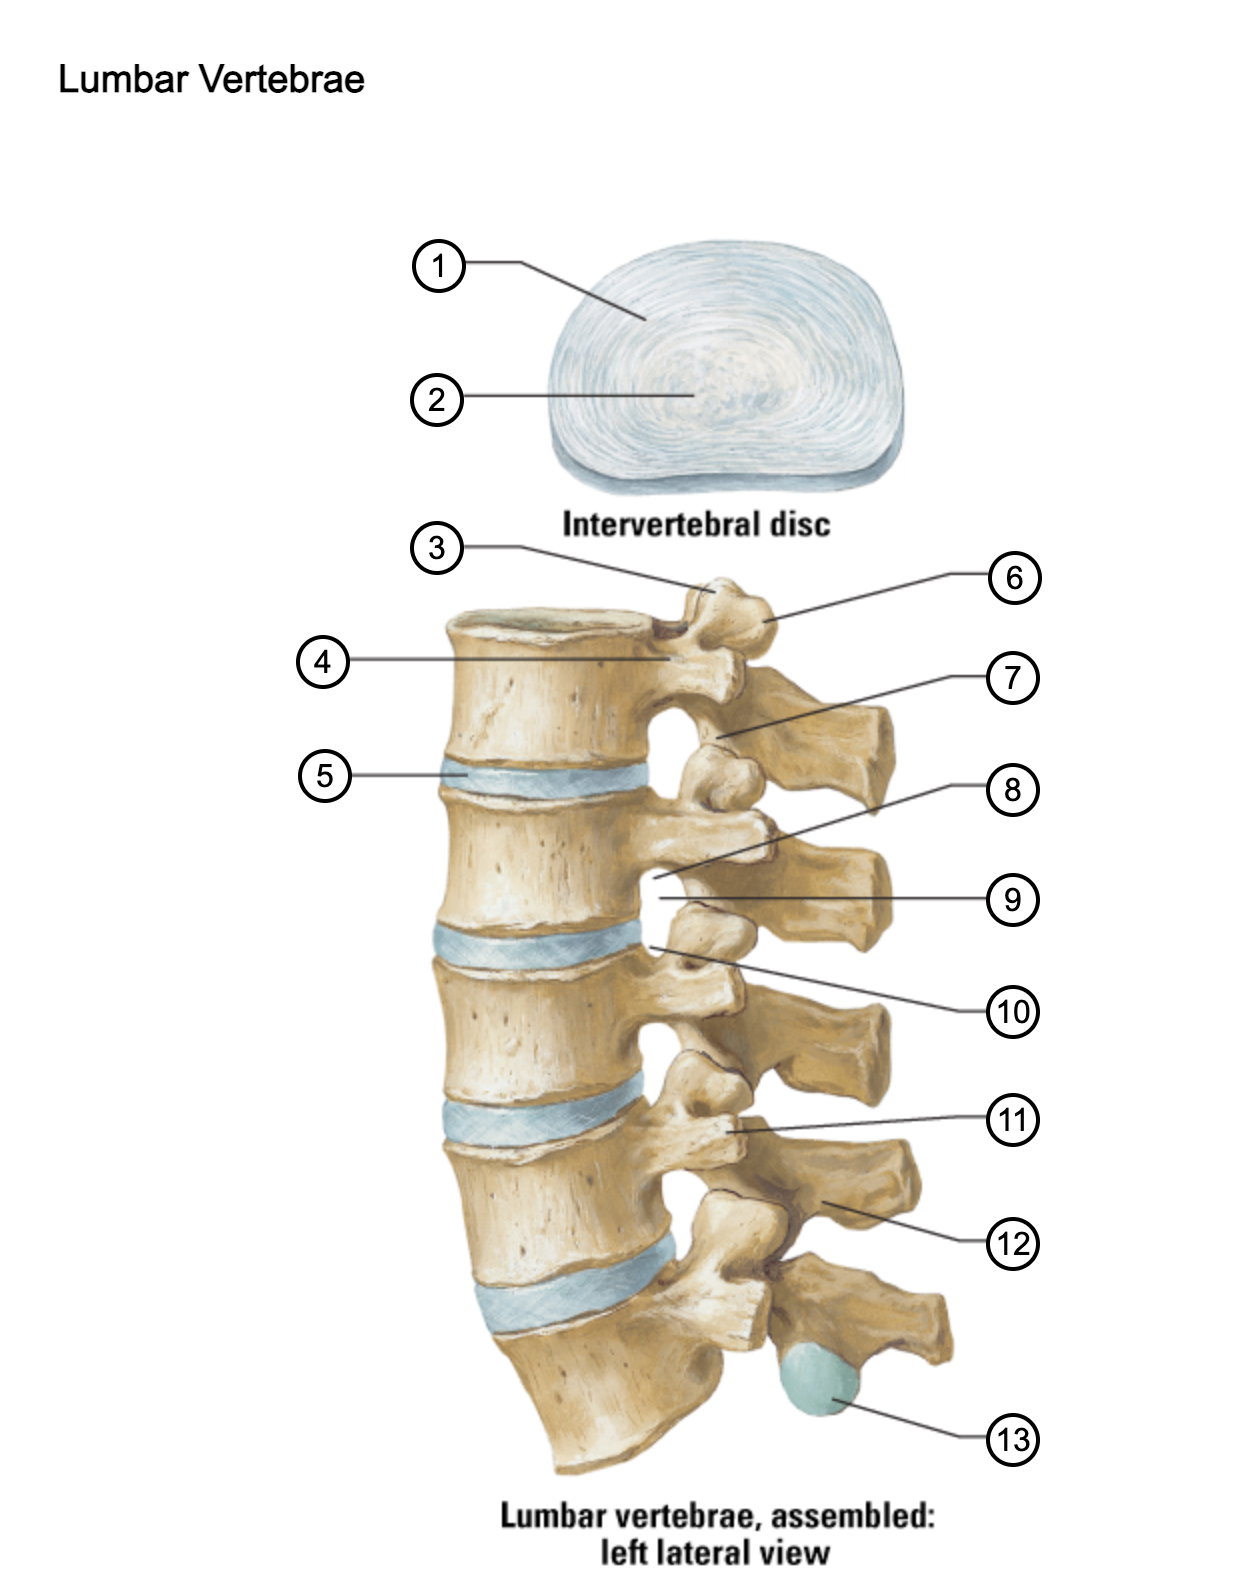

1

anulus fibrosus

2

nucleus pulposus

3

superior articular process

4

pedicle

5

intervertebral disc

6

mammillary process

7

inferior articular process

8

inferior vertebral notch

9

intervertebral notch

10

superior vertebral notch

11

transverse process

12

lamina

13

inferior articular facet